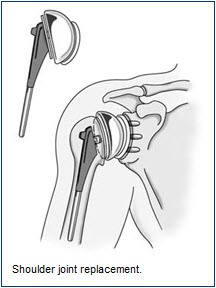

Surgical TreatmentThere are several different types of shoulder replacements. The usual total shoulder replacement involves replacing the arthritic joint surfaces with a highly polished metal ball attached to a stem, and a plastic socket.

The components come in various sizes. If the bone is of good quality, your surgeon may choose to use a non-cemented or press-fit humeral component. If the bone is soft, the humeral component may be implanted with bone cement. In most cases, an all-plastic glenoid component is implanted with bone cement. Implantation of a glenoid component is not advised if:

Patients with bone-on-bone osteoarthritis and intact rotator cuff tendons are generally good candidates for conventional total shoulder replacement.

Depending on the condition of the shoulder, your surgeon may replace only the ball. Sometimes, this decision is made in the operating room at the time of the surgery. Some surgeons replace the ball when it is severely fractured and the socket is normal.